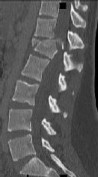

Figures 1 and 2 are CT scans obtained from a 68-year-old man who has had

progressive neck pain and stiffness, worsening gait imbalance, upper extremity weakness, early muscle fatigue, difficulty with fine motor control, and difficulty with activities of daily living over the past few years. On physical examination, he has a wide based stiff legged gait, generalized upper extremity weakness, dense sensory loss in the upper and lower extremities, and markedly brisk reflexes. What is the most appropriate treatment for this patient?

4. Posterior cervical laminoplasties from C3-6 Discussions: D

This patient has progressive myelopathy secondary to ossification of the posterior longitudinal ligament. Diagnostic imaging reveals multilevel cervical cord compression from C4-6. The patient has maintained reasonable cervical lordosis. A posterior procedure such as multilevel laminoplasty

decompresses the spine, is motion preserving, and has a low complication rate. Observation and cervical epidural injections are not viable options in patients with progressive myelopathy. Anterior cervical decompression, including corpectomy, is an option; however, anterior procedures have an increased risk of complications such as dural tear or cerebrospinal fluid leak. The axial CT image shows a "double layer" sign, which is consistent with dural ossification and increases the risk of dural injury with anterior decompression